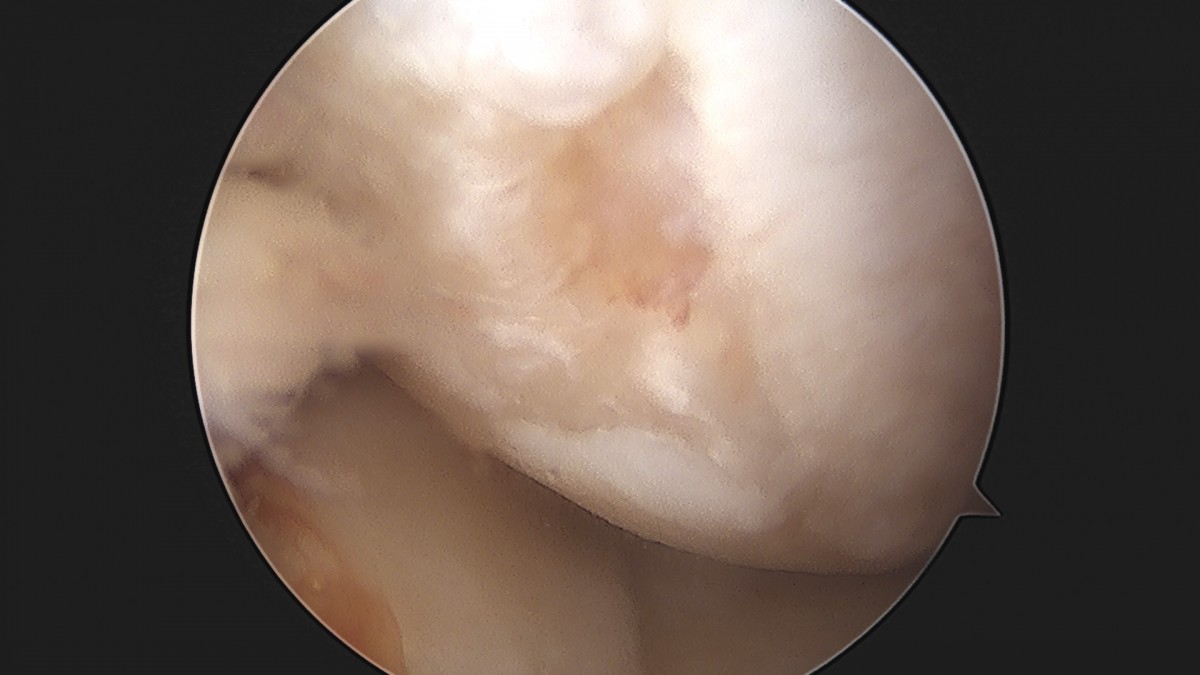

이재상원장님 무릎 반월상 연골판 절제술 김민O 환자

작성자 최고관리자 댓글 0건 조회 365회 작성일 25-09-16 16:10